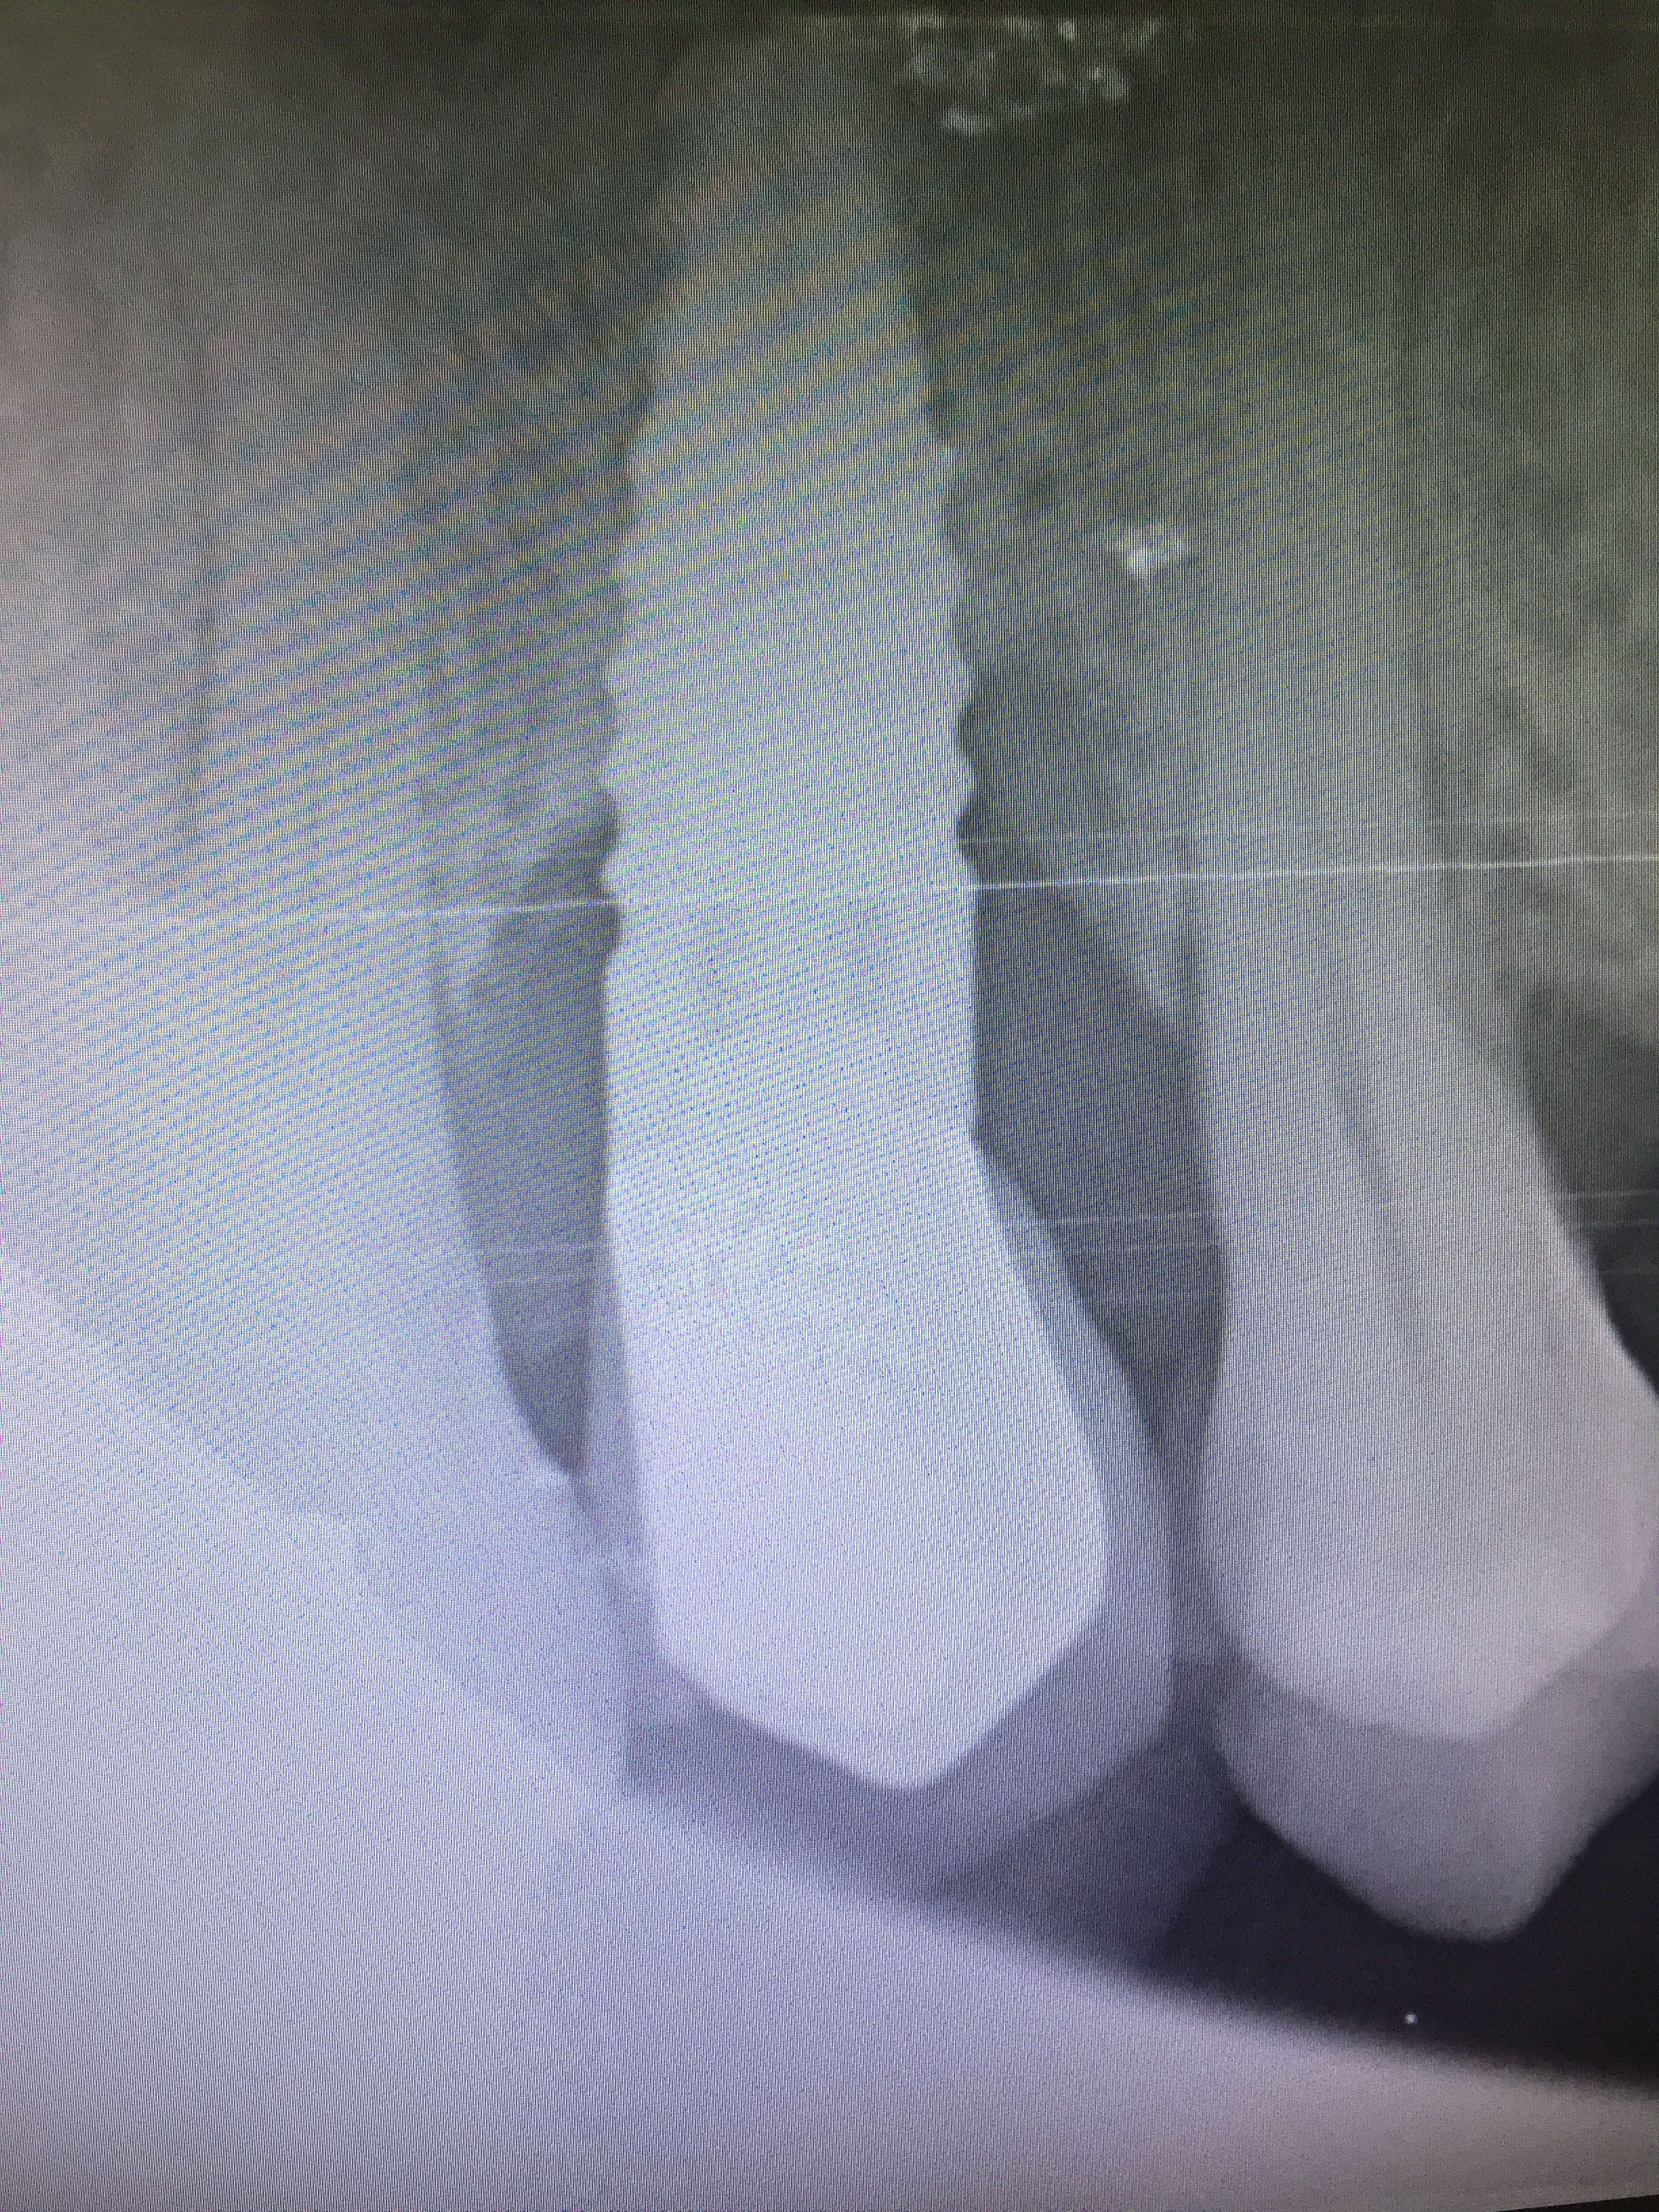

Reconnaissez vous cet implant?

La patiente me dit que c’est un Tbr et qu’il a été posé il y a une dizaine d’années.

peut etre un conic?

C'est pas un fotopourri ø 3,5 ?